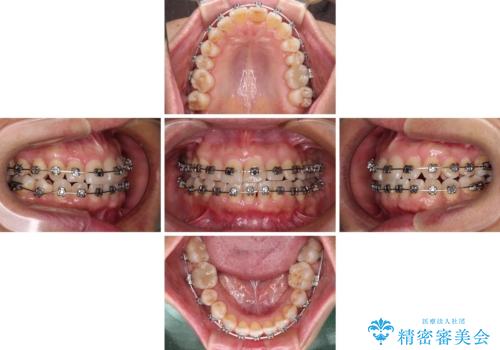

- メタルブラケット

- 1年8ヶ月

- 10-30回